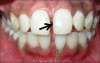

Turner's syndrome is a disorder in females characterized by the absence of all or part of a normal second sex chromosome. It is typically characterized by the combination of physical features and cytogenetics in females. Physical features include short stature, primary amenorrhea, hypogonadism, low hair line at the back of the neck, and digital anomalies. Most affected patients have a 45XO monosomy, but the presence of an abnormal chromosome or mosaicism of 45X with another cell line can also fulfill the criteria. Features seen in the oral cavity of patients diagnosed with Turner's syndrome include high palatal vault, hypoplastic mandible, prematurely erupting teeth, and orthodontic anomalies. A case of Turner's syndrome with localized aggressive periodontitis has been reported here.